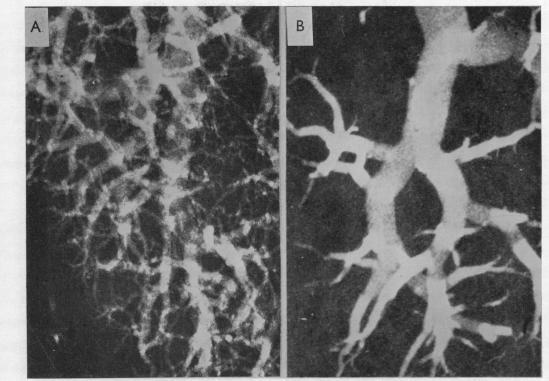

Pulmonary hypertension in mitral stenosis.

Br Heart J. 1957 Oct;19(4):457-72. doi: 10.1136/hrt.19.4.457.